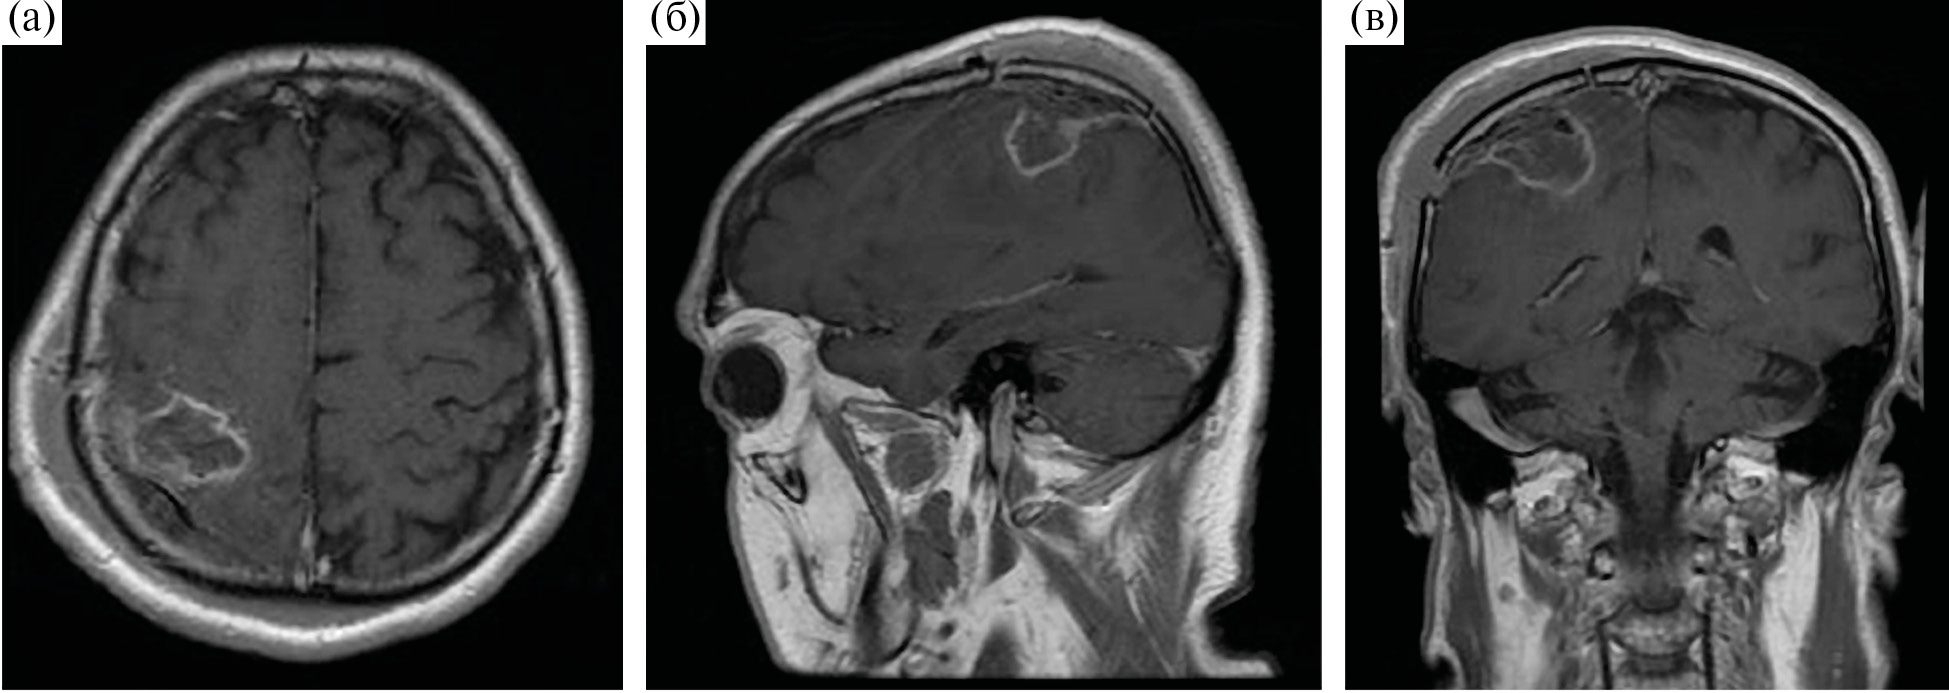

По данным контрольной СКТ сразу после операции, интракраниальных осложнений не выявлено, по данным контрольной МРТ, выполненной на следующие сутки, – тотальное удаление контрастируемой части опухоли (рис. 6).

Рис. 6. Контрольная МРТ у пациента после микрохирургического удаления глиобластомы правой теменной доли, режим Т1 + С. (а) – аксиальная проекция; (б) – сагиттальная проекция; (в) – фронтальная проекция.

Fig. 6. Postoperative MRI.